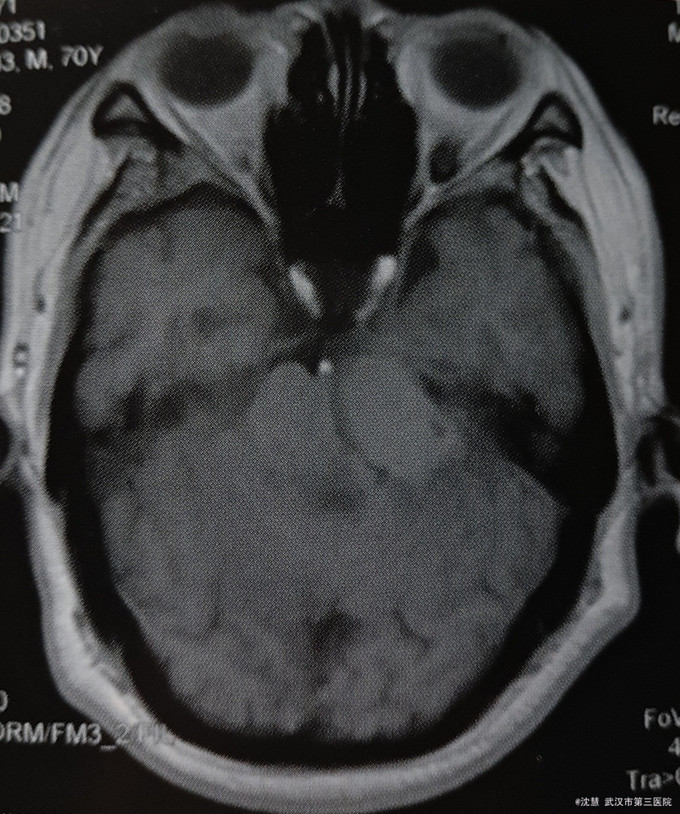

患者男,70岁,主因左耳听力减退20余年,行走不稳半月入院。患者20余年前出现左耳听力减退,无其他不适。半月前出现行走不稳,向左侧倾倒,伴左侧耳鸣、左侧面部麻木,无意识障碍、头痛,无吞咽困难、饮水呛咳、声音嘶哑等。

查体:生命体征平稳,心肺腹体检无明显异常。专科检查:左眼外展稍受限,左侧咀嚼肌力量减弱,左侧颜面部痛温觉减退,左侧听力减退,左侧指鼻、指指及跟膝胫实验欠协调,Romberg征阳性。 影像学:头部MRI:左侧桥小脑角占位,脑干受压。

诊断:桥小脑角肿瘤 治疗:全麻下左侧桥小脑角区脑膜瘤切除术 病理:(左侧桥小脑角区)脑膜瘤(WHO I级)